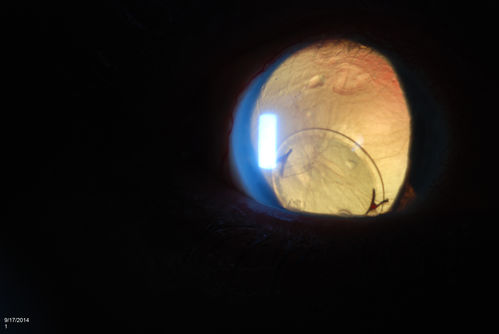

Free Floating Dislocated Lens in Vitreous

Patient comes in aphakic with dislocated lens floating to the back of the eye when laying down. Lens is  laying up against the endothelium of the cornea when patient is right side up..